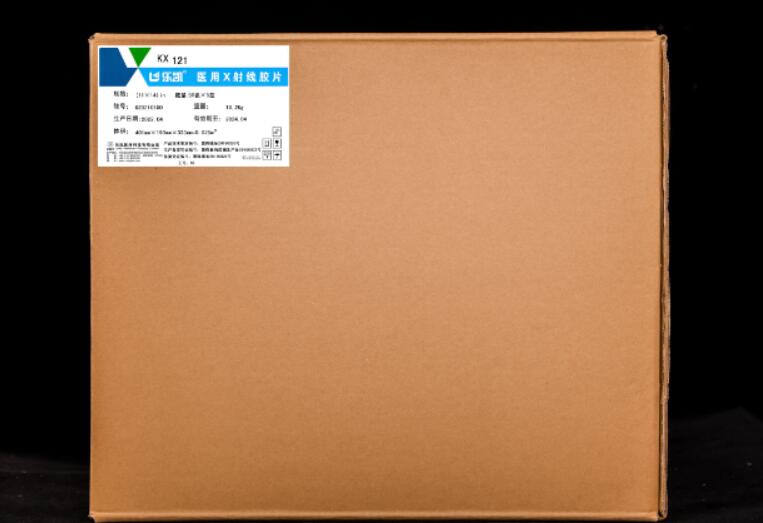

Medical Blue&Green X-ray Film

The product is a general green sensitive medical x-ray film, which has green sensitive emulsion layers on both sides of blue polyester base sheet.